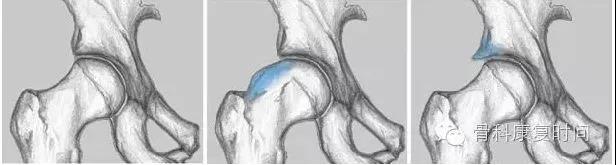

分 型

1、凸轮撞击型(cam-type ):股骨头、颈间的凹陷不足。2、钳夹撞击型(pincer-type):髋臼解剖异常:髋臼后倾、尤其是上1/3的后倾;髋臼过深;髋臼前突。3、混合型

2、钳夹撞击型

- 通常存在于喜好活动的中年女性。

股骨头颈连接处和髋臼缘的异常接触,反复的撞击接触导致髋臼唇的变性,进一步引起髋臼内部囊性变以及髋臼唇周的骨化和髋臼加深。该慢性损伤常位于髋臼软骨周围的狭窄长条状区域。髋臼唇周围的变性通常以骨化形式表现。